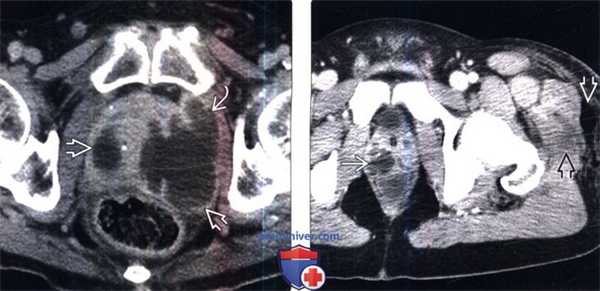

(Слева) КТ с контрастированием, аксиальный срез: увеличенная предстательная железы с множественными абсцессами. На изображении слева абсцесс распространился за пределы капсулы в перипростатическое пространство.

(Справа) КТ с контрастированием, аксиальный срез: газ и жидкость в мягких тканях ягодичной области и бедра, а также множественные жидкостные образования в простате. Это говорит о распространении инфекционного процесса, который затронул всю промежность и часть малого таза.